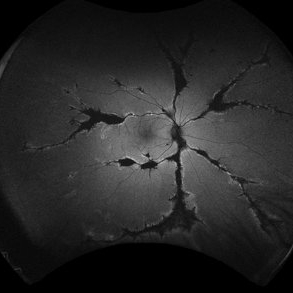

Pigmented Paravenous Retinochoroidal Atrophy (PPRCA) Pigmented Paravenous Retinochoroidal Atrophy (PPRCA)Jun 27 2025 by Maria Letícia Costa Holanda Fundoscopy of a 42-year-old asymptomatic man with pigmented paravenous chorioretinal atrophy. Pigmented paravenous retinochoroidal atrophy (PPRCA) is a rare disorder of unknown etiology. The disease is characterized by pigment accumulation along the distribution of retinal veins. The findings are usually incidental with minimal effect on vision. Photographer: Guilherme da Cruz Reis, CLINOS Eye Hospital - Feira de Santana (BA),Brazil Condition/keywords: pigmented paravenous chorioretinal atrophy (PPCRA)